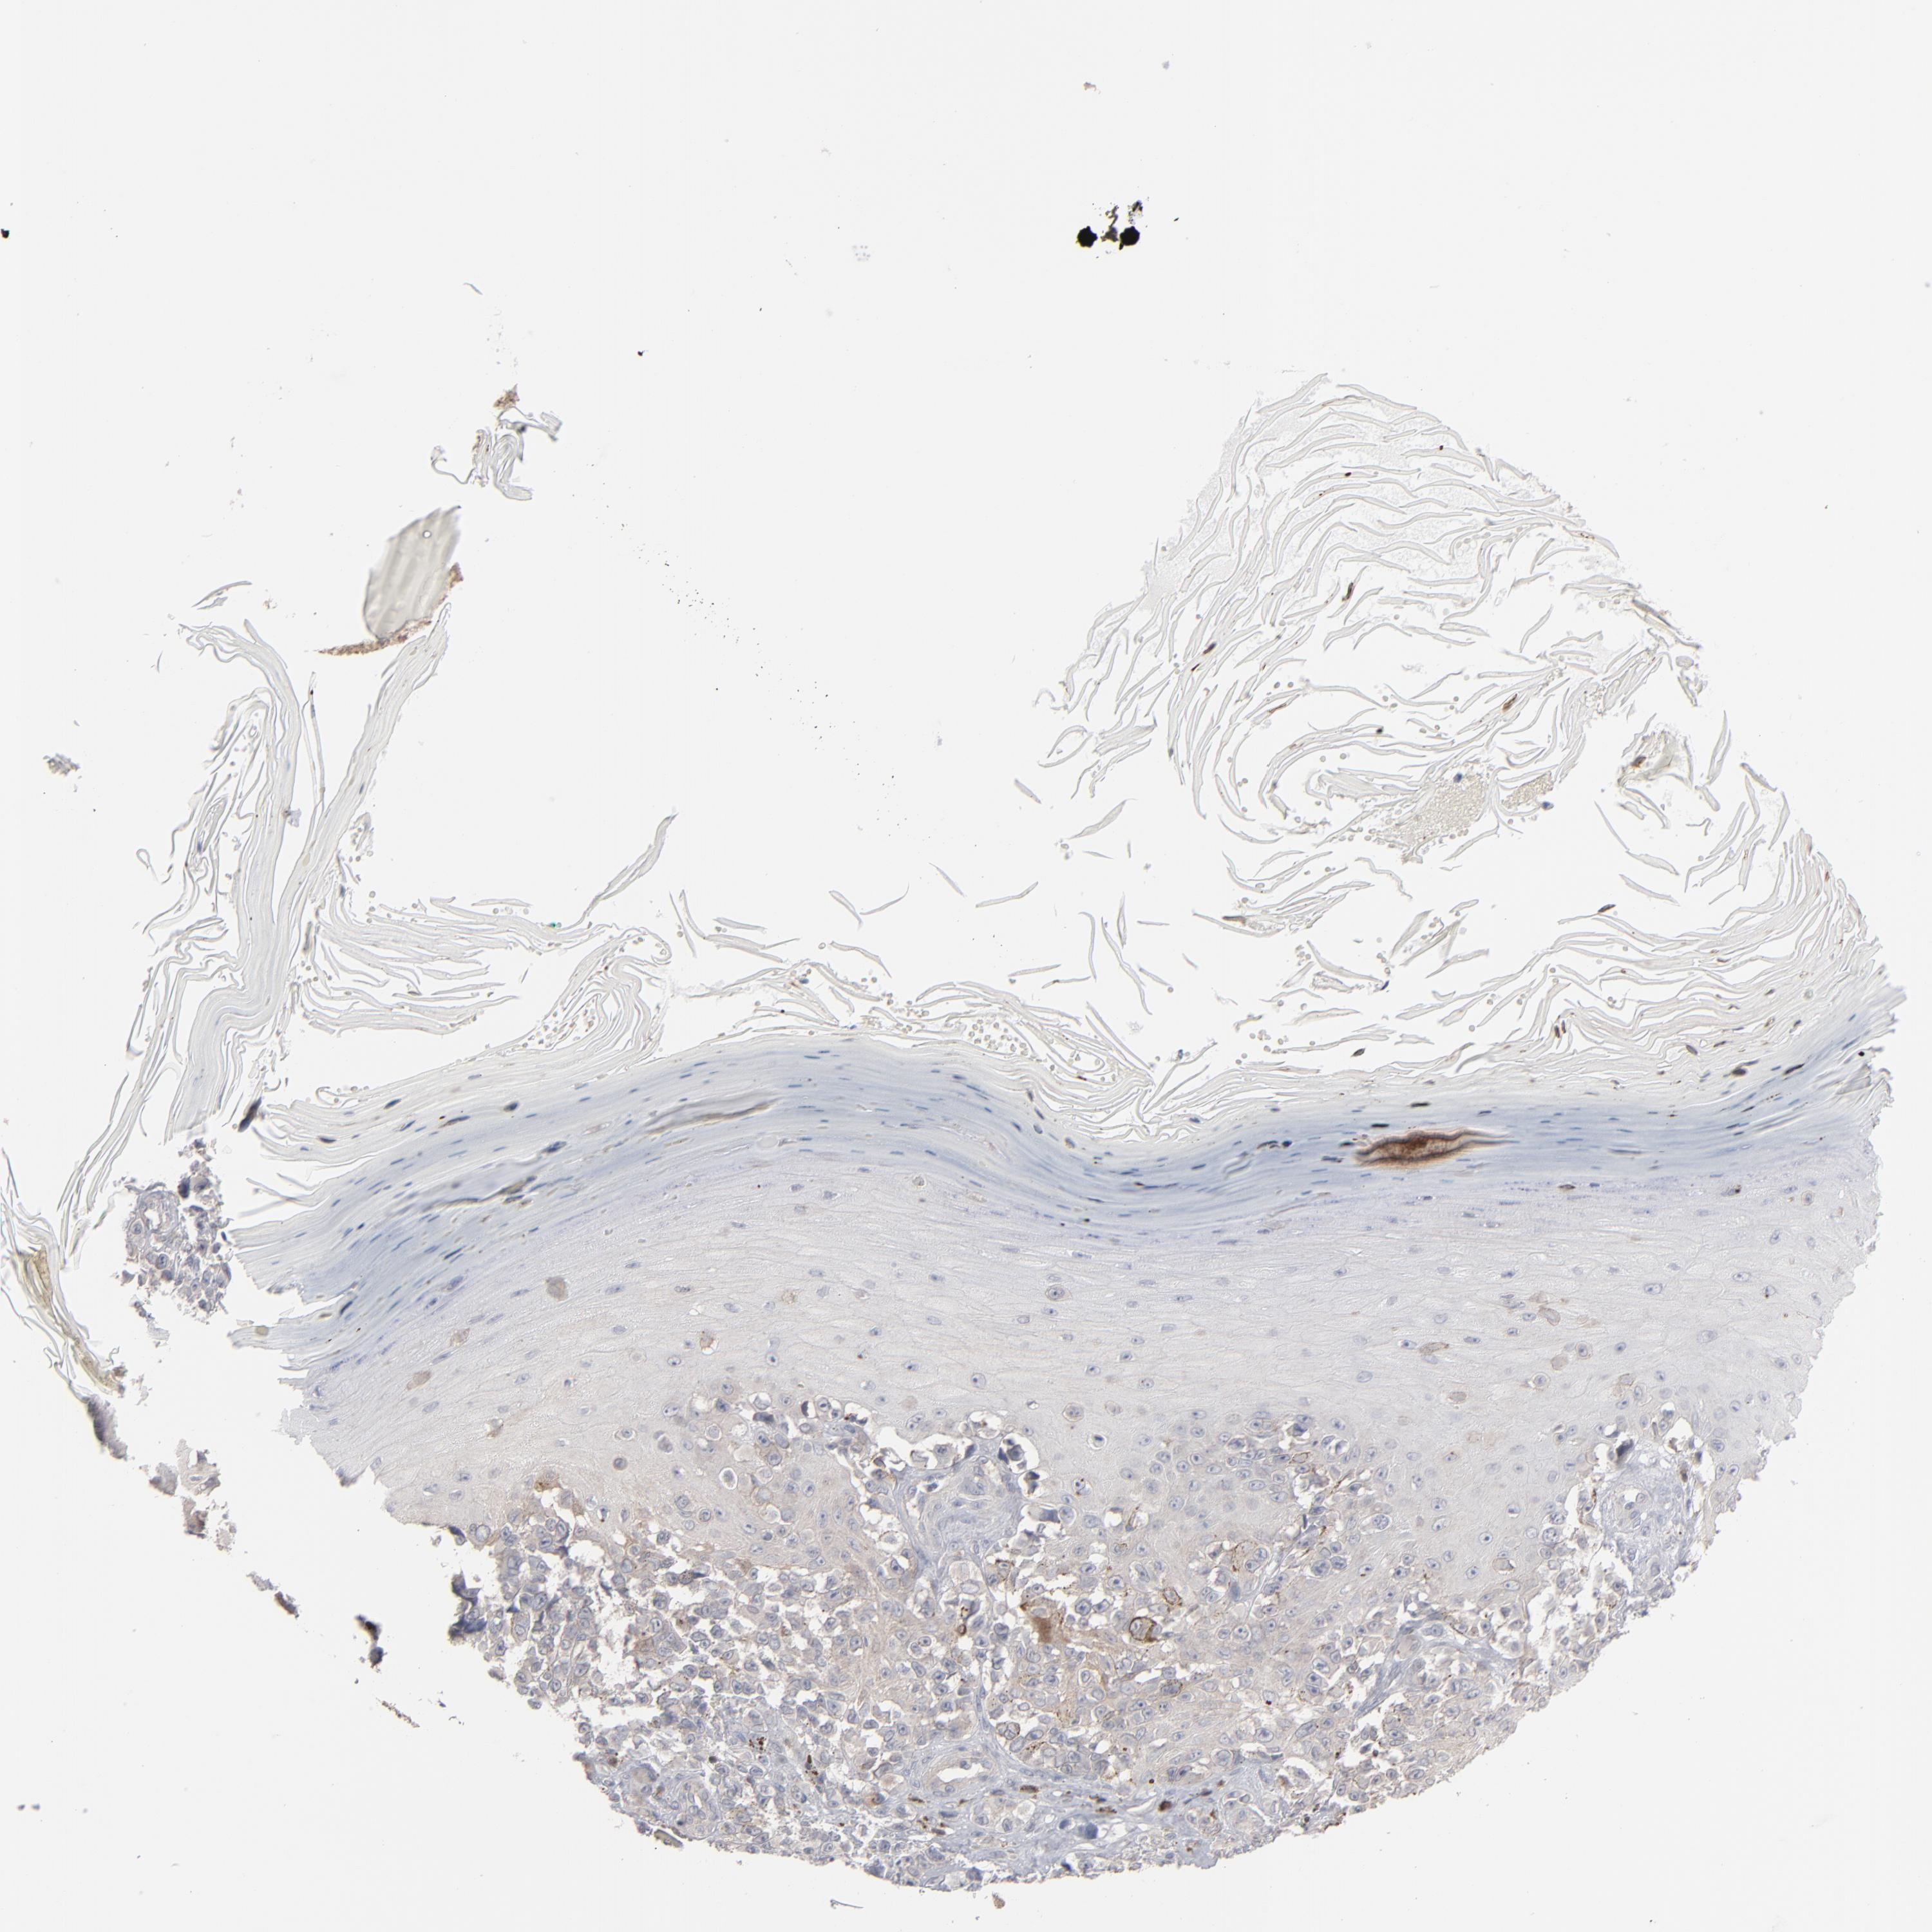

MELANOMA - Protein expressioni

A mouse-over function shows sample information and annotation data. Click on an image to view it in a full screen mode. Samples can be filtered based on level of antibody staining by selecting one or several of the following categories: high, medium, low and not detected. The assay and annotation is described here.

Note that samples used for immunohistochemistry by the Human Protein Atlas do not correspond to samples in the TCGA dataset.

Antibody stainingi

Antibody staining in the annotated cell types in the current human tissue is reported as not detected, low, medium, or high, based on conventional immunohistochemistry profiling in selected tissues. This score is based on the combination of the staining intensity and fraction of stained cells.

Each image is clickable and will lead to virtual microscopy that enables deeper exploration of all samples and also displays staining intensity scores, fraction scores and subcellular localization as well as patient and tissue information for each sample.

Antibody HPA001860

Antibody CAB013108

Malignant melanoma, NOS

Malignant melanoma, Metastatic site